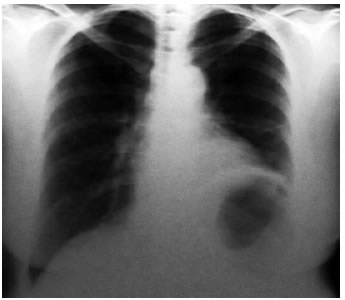

Se describe el caso de una mujer, de 50 años de edad. La paciente es derivada de Bahía Blanca, Provincia de Buenos Aires, por hallarse, en razón de un chequeo, una radiografía (Rx) de tórax con una imagen tumoral en región parahiliar izquierda de bordes bien delimitados (Figura 1).